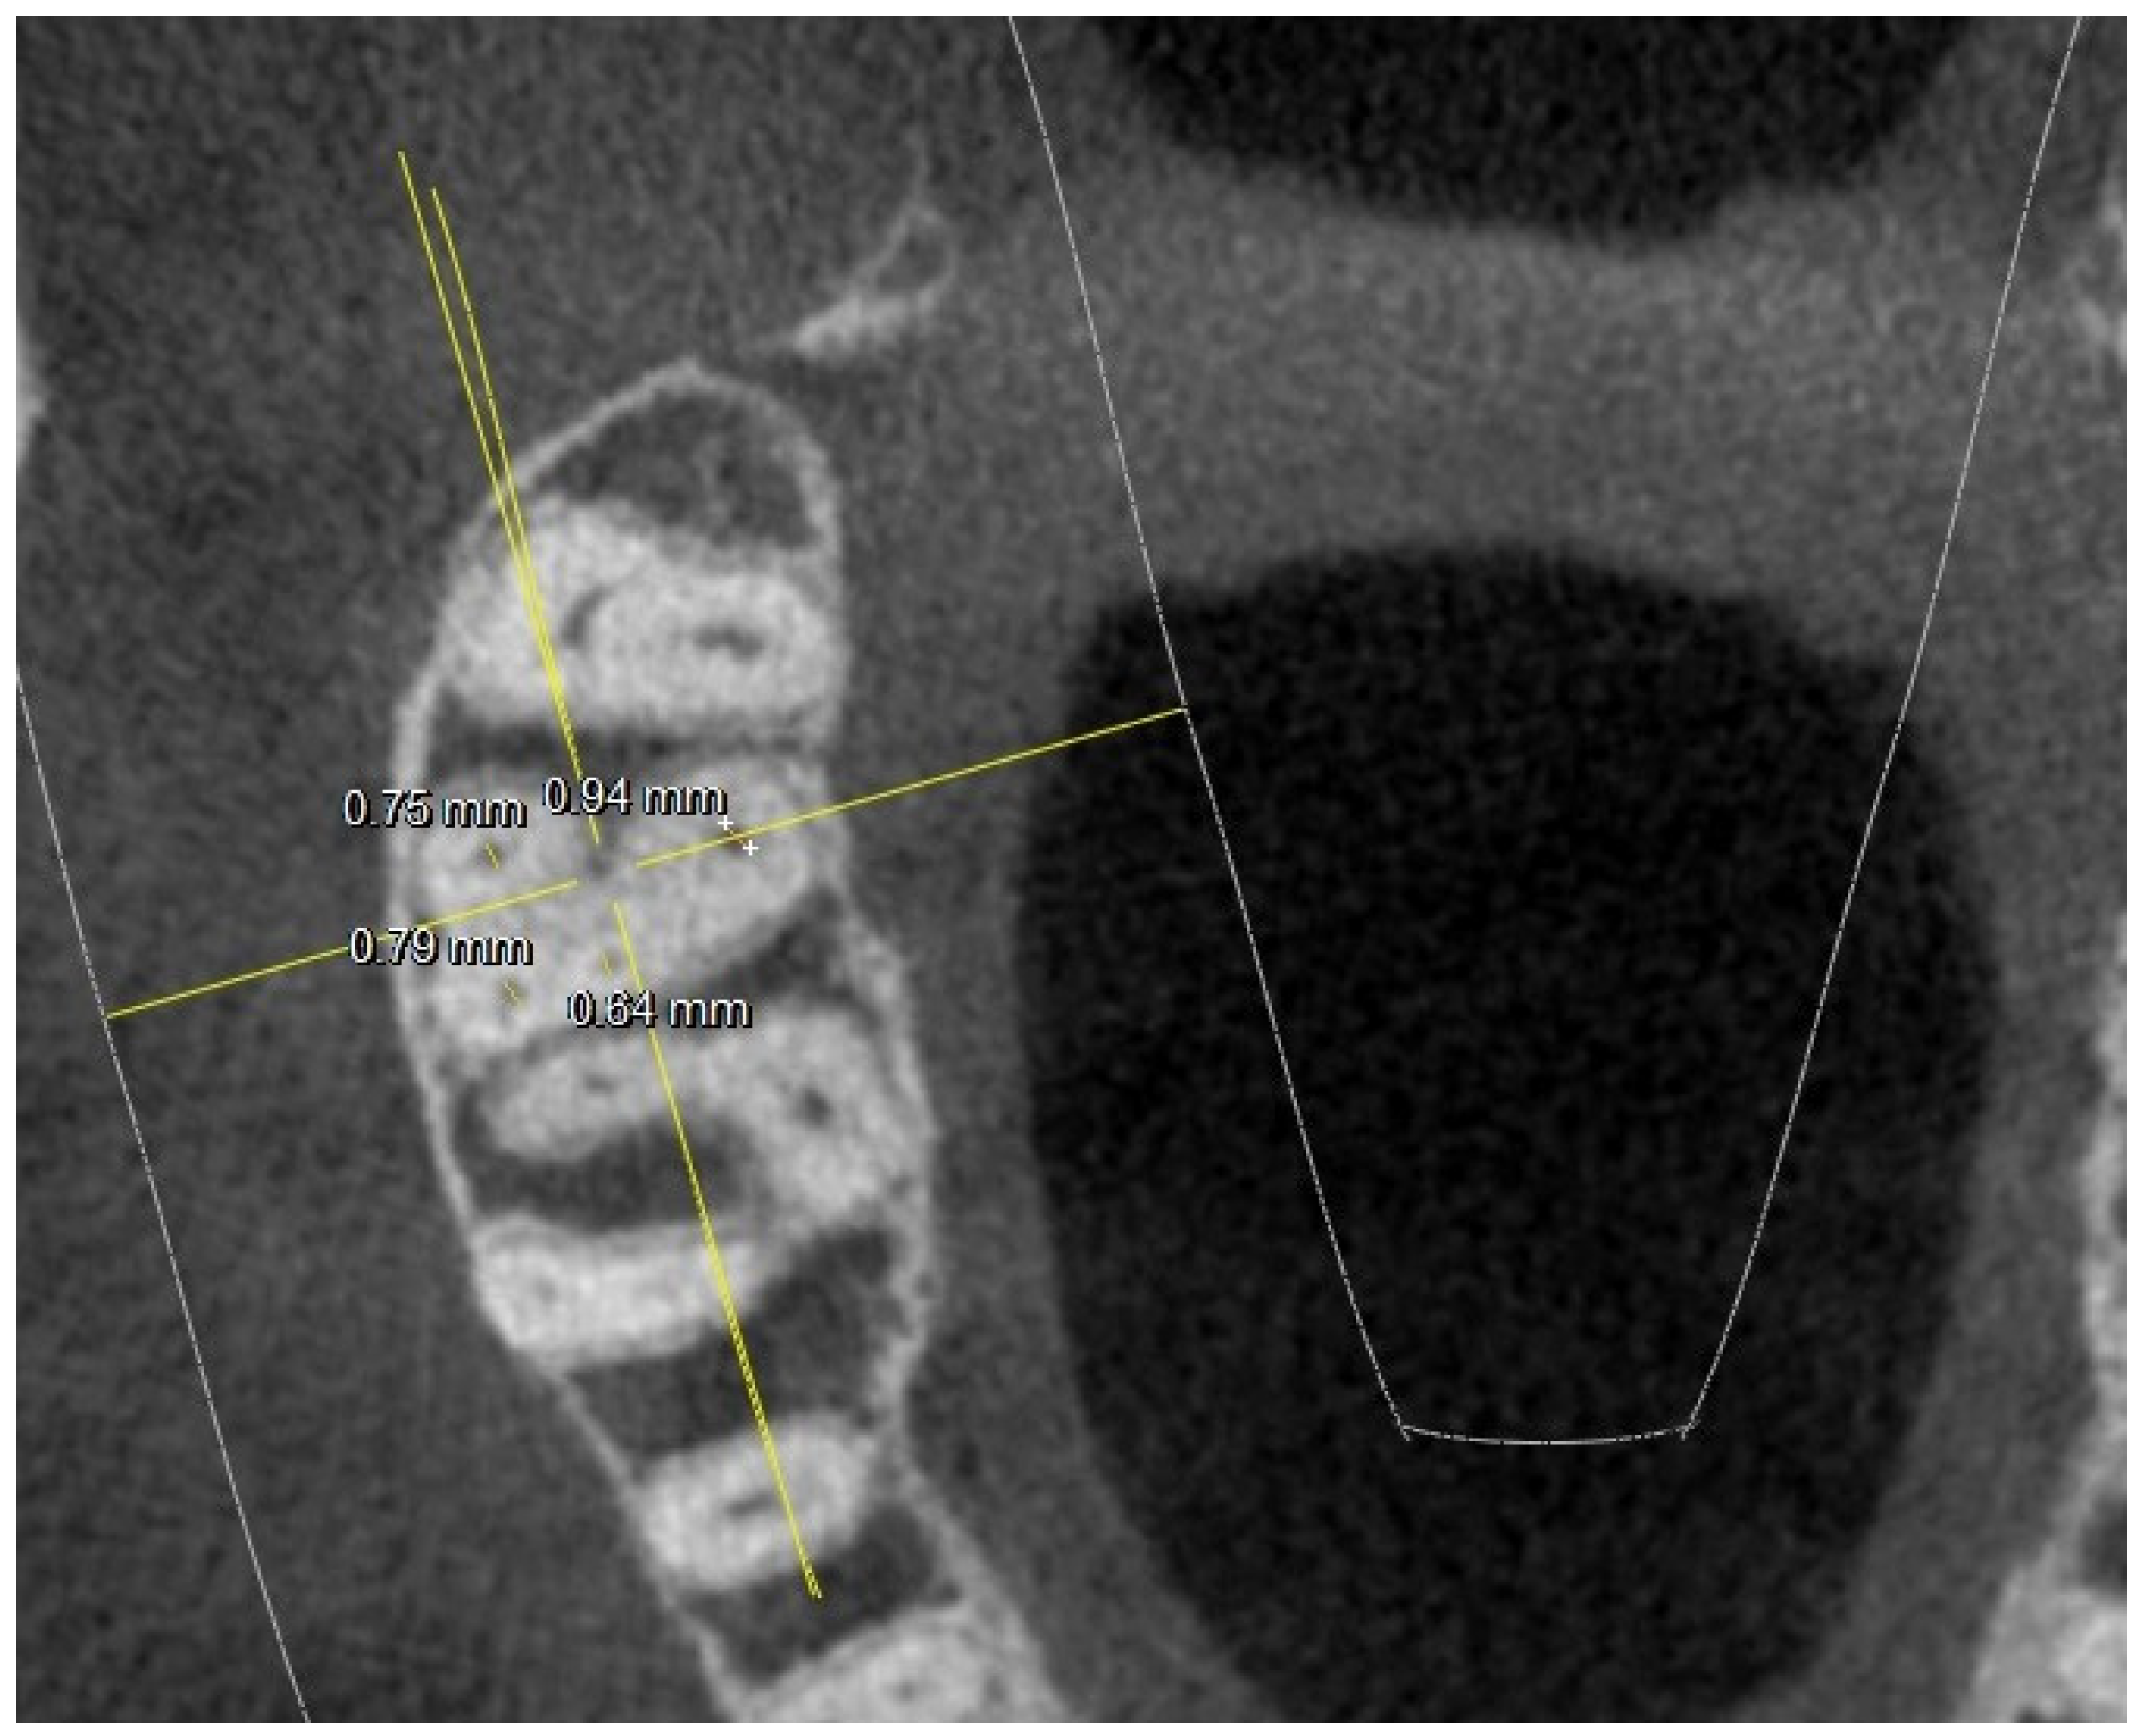

- diameter of root canal orifices;

| 5 mm from the CEJ: MB diameter | 0.74 | 0.26 | 0.85 | 0.21 | 0.74 | 0.24 | 0.8 | 0.22 | ||

| DB diameter | 0.79 | 0.14 (2 NO) | 0.65 | 0.11 (1 NO) | 0.75 | 0.12 (1 NO) | 0.68 | 0.12 (3 NO) | ||

| Palatal diameter | 1.19 | 0.07 | 1.1 | 0.06 | 1.35 | 0.06 | 1.19 | 0.06 | ||

| MB2 diameter | 0.42 | 0.6 (2 NO) | 0.47 | 0.5 (7 NO) | 0.47 | 0.7 (3 NO) | 0.42 | 0.4 (11 NO) | ||